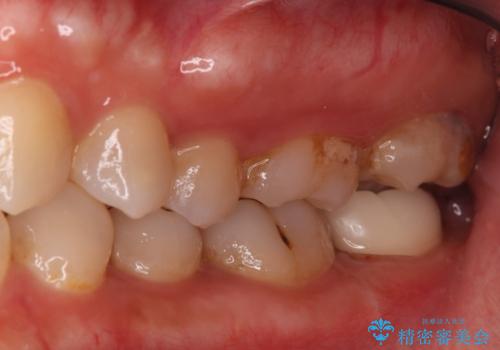

- 昨日からのズキズキとした激しい痛みを主訴にご来院されました。レントゲンおよび歯髄診察の結果、不可逆性の歯髄炎(歯の神経の重度の炎症)と診断。歯を残すことを第一に、まず痛みの原因である神経を取り除く根管治療を提案しました。また、虫歯が歯肉の下まで深く進行していたため、根管治療後に歯周外科処置を行い、最終的に精密なセラミッククラウンで修復する、総合的な治療計画を立案しました。

治療はまず、根管治療から始め、感染した神経を徹底的に除去することで、痛みをすぐに解消しました。再発を防ぐため、ラバーダムや顕微鏡を使って、根管内を丁寧に、そして精密に処置しました。次に、深い部分の虫歯を確実に治療するため、歯周外科処置を行い、治療しやすい環境を整えました。最後に、機能と見た目に優れたセラミッククラウンを作製・装着。根管治療から外科処置、審美修復までを一貫して行うことで、再発リスクの低い、長期的に安定して使える奥歯を取り戻していただけました。